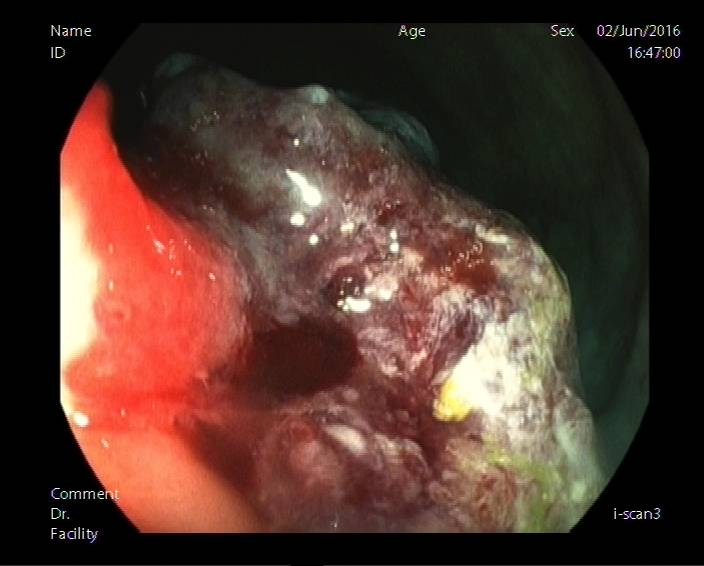

图6a:距肛门3cm可见一直径约4cm隆起,占肠腔1/2,表面粗糙,溃烂。使用蒸馏水对病灶表面冲洗去除黏液,可见病灶表面无构造(无pit)区域或构造紊乱,可初步判定为V型pit。

图6b:观察病灶顶端,仍见无构造区域。依旧考虑V型pit。且病灶位于直肠,病灶表面可见白斑,病灶表面凹凸不平,均提示sm癌浸润可能性大(参考图5),建议外科手术。

后患者就诊于肛肠外科行手术治疗,病理示:1.(直肠)中分化腺癌,部分为粘液腺癌(肿块一个5×4×1.5cm,菜花状),侵及全层,(远、近断端)未见癌,(肠旁)淋巴结见癌转移(12/12)。